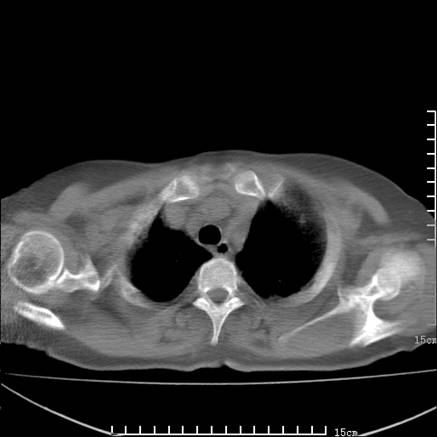

女,王某,58岁,咳嗽三个月余,基层医院二个月前诊为肺结核,用抗结核药二个月无明显疗效。

心包积液致肺瘀血.右侧周围型肺癌伴肺内转移,中间裂积液,叶间胸膜肥厚.右上肺大泡,右侧胸膜肥厚.

双肺继发型tb,心功能不全并肺淤血、心包、双侧叶间裂积液,肺大泡,右下胸膜肥厚钙化。